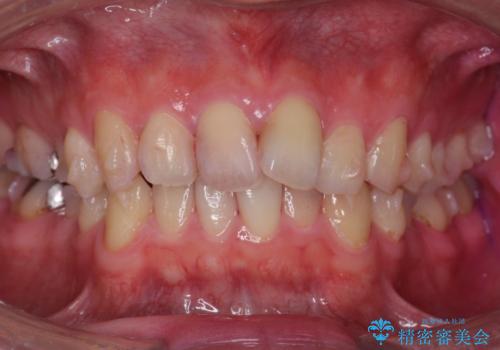

奥歯のかみ合わせを特に変えず、前歯の並びを整える治療をおこないました。

奥歯のかみ合わせは1本分ずれているとはいえ、1歯対2歯の交互のかみ合わせになっているため、そのままにしてもそこまで大きなデメリットはありません。

右上のかみ合わせをそのままにするため、上下の正中は合わない仕上がりとなります。

今回は右のかみ合わせはそのままにしました。左は特に初めから問題ない状態でした。

右のかみ合わせを変えず部分矯正にしたことによって、治療が短期間で済み、また、ワイヤーでなくインビザラインで治療が可能、歯も抜かなくて済むなどメリットの多い方法であるといえます。